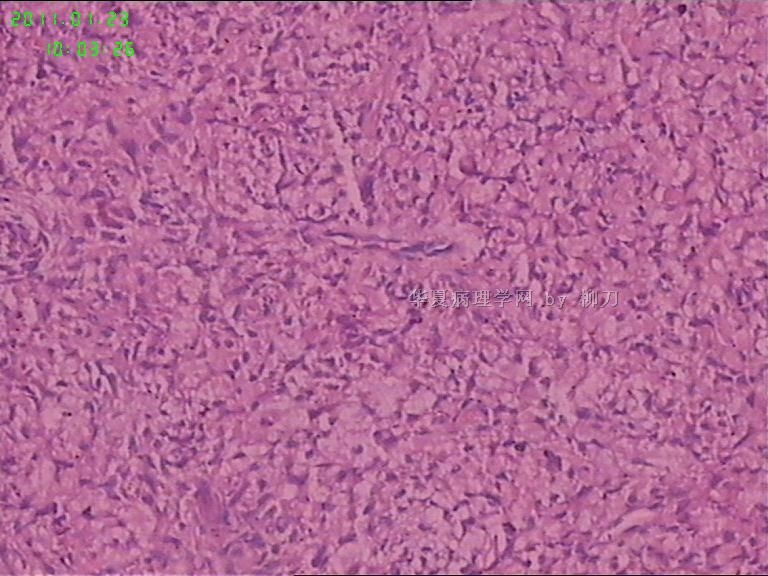

姓    名: ××× 性别:  男 年龄:  36

标本名称:  腮腺包块

简要病史:  包块2年多,数月来增大。

2,3图是前2个结节的镜下表现,梭形皮瓣是皮内痣。4以后是具完整包膜的肿块表现,核分裂少见。

我们考虑肌上皮瘤,少见多怪,老师们请多指教。

现有图像上看考虑肌上皮瘤。如果粘液样区域多,要考虑多形性腺瘤。

可以做一下组化:CK、SMA、S-100、GFAP、P63。

肌上皮瘤